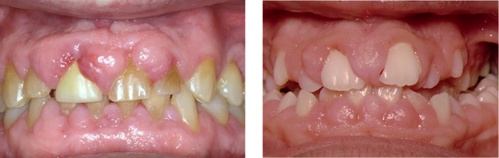

Patients taking certain drugs for existing conditions such as calcium channel blockers for hypertension, phenytoin for epilepsy and ciclosporin, an anti-rejection drug which can also be prescribed for some autoimmune disorders, may be at risk of drug-influenced gingival enlargement (see figure: Drug-influenced gingival enlargement). In cases where gingival overgrowth is limited, the condition may respond to non-surgical treatment. In addition to periodontal management, drug substitution should be considered and can be discussed with the patient’s general medical practitioner. Periodontal surgery may be required to reduce and recontour the tissue at sites of gingival enlargement. However, the condition may recur in susceptible individuals and the surgery may need to be repeated.

Examples of drug-influenced gingival enlargement